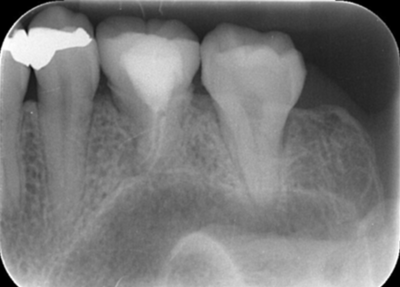

初診時デンタルX線写真

初診時デンタルX線写真とCT画像。

根管外に不透過像とそれを取り囲む透過像を認める。

コアを除去すると、分岐部へつながるパーフォレーションを認めた。

これが排膿の原因であったため、保存は困難と判断した。